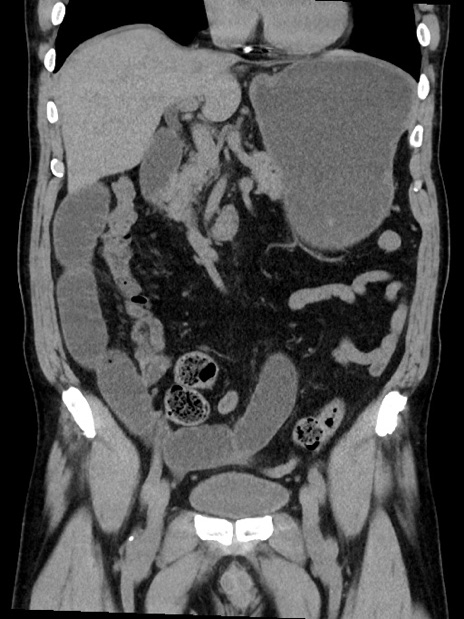

症例35(冠状断像)

【症例】70歳代 男性

【主訴】腹部膨満、嘔吐

【現病歴】昨日より腹部膨満感出現。本日増悪し、仙痛出現。嘔吐あり、受診。

【既往歴】糖尿病、胆摘後

【身体所見】BP 149/80mmHg、HR 74/min、BT 35.9℃、腹部:膨満、軟、圧痛なし。腸雑音減弱あり。上腹部正中切開瘢痕あり。

【データ】WBC 13500、CRP 1.72